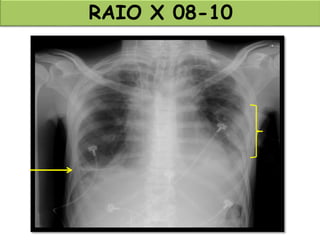

RAIO X 08-10

TOMOGRAFIA 08-10